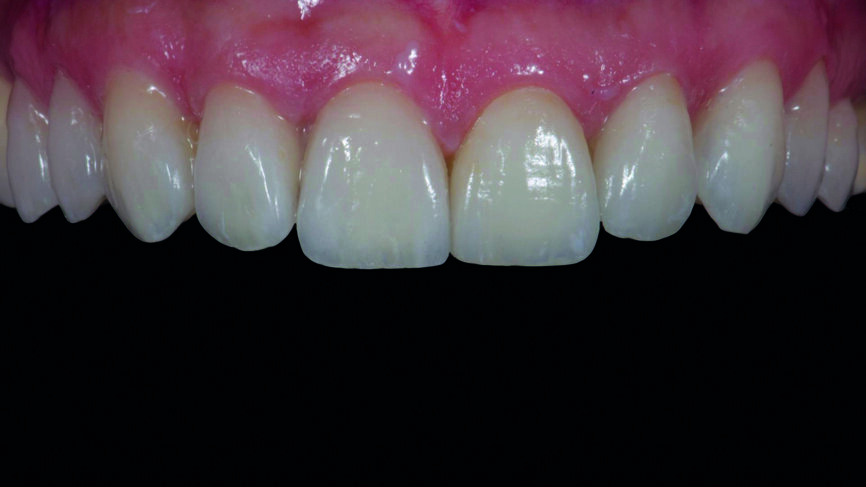

Fig. 16f : Résultat final immédiatement après le retrait de la digue en caoutchouc.

Fig. 17a : Résultat final une semaine plus tard.

Fig. 17b : Résultat final une semaine plus tard, vue de face

Le clinicien et la patiente ont décidé subjectivement un scellement des facettes en céramique feldspathique en raison des légères différences dans la longueur des incisives centrales des deux jeux. Les procédures adhésives ont suivi (Figs. 16a–f) et des photographies intra-orales et extraorales ont finalement été prises une semaine plus tard (Figs. 17a–e).